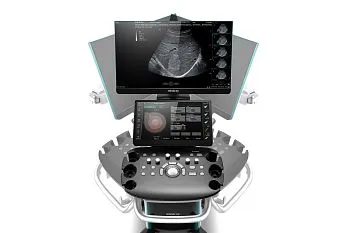

Ультразвуковой аппарат GE HealthCare Vivid T9

Клинические изображения

Описание

GE HealthCare Vivid T9 — универсальная ультразвуковая система для кардиологических и общих исследований у взрослых и детей, с расширенными возможностями диагностики в акушерстве и гинекологии, ангиологии, урологии, исследовании органов брюшной полости, малых органов, поверхностных структур и мышечно-скелетной системы, урологии, транскраниальных и чреспищеводных исследованиях. Ультразвуковая система среднего класса Vivid T9 объединяет признанное качество визуализации в кардиологии, характерное для линейки Vivid, и возможности широкого использования в общей диагностике, которыми отличается линейка LOGIQ.

GE HealthCare Vivid T9 поддерживает широкий спектр датчиков, включая специализированные кардиологические и обще-диагностические модели. Функции Speckle Tracking, AutoEF и Strain Imaging позволяют детально оценивать деформацию миокарда, а режимы 2D, M-Mode и допплерография обеспечивают комплексный анализ сердечно-сосудистой системы. Благодаря эргономичному дизайну и продуманному интерфейсу аппарат удобен в использовании

Система предназначена для обеспечения удобства работы и транспортировки в различных условиях. Ее интуитивно понятный пользовательский интерфейс представляет собой саму консоль Vivid со всеми преимуществами ее приложений, функций, оптимизированного рабочего процесса, надежности и простоты в использовании. GE Vivid T9 идеально подходит для использования в многопрофильных медицинских учреждениях, специализированных диагностических центрах и кардиологических клиниках.